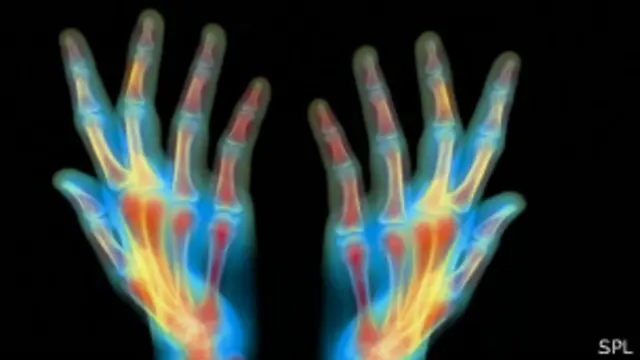

El experto considera que primero se podría regenerar cartílago o piel, que son tejidos que no se regeneran, avances que serían respectivamente cruciales en personas que sufren de artritis o víctimas de quemaduras.